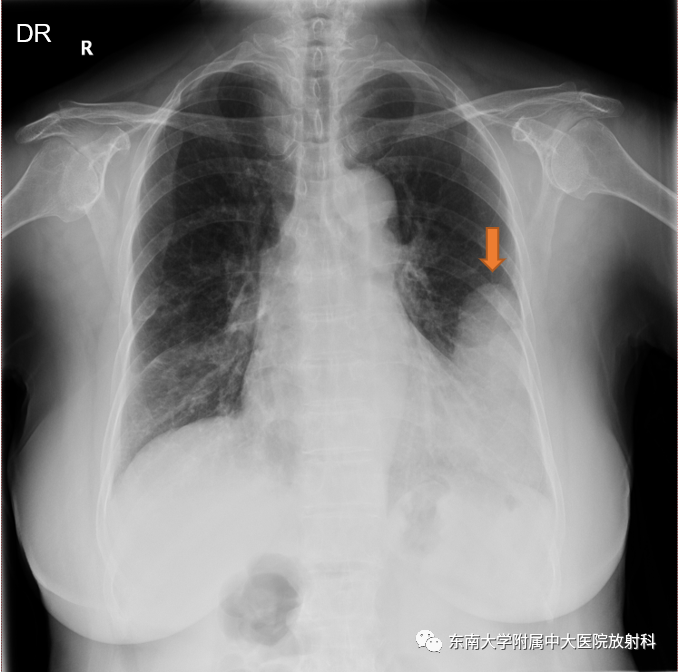

病例2

女,55岁

主诉:发现胸腔占位一月余

现病史:患者1月前查胸部CT平扫:右前下胸包裹性积液;胸部CT增强:右侧胸腔占位,未予特殊治疗,2天前深吸气后出现右侧胸部隐痛不适,偶有咳嗽咳白粘痰,量少